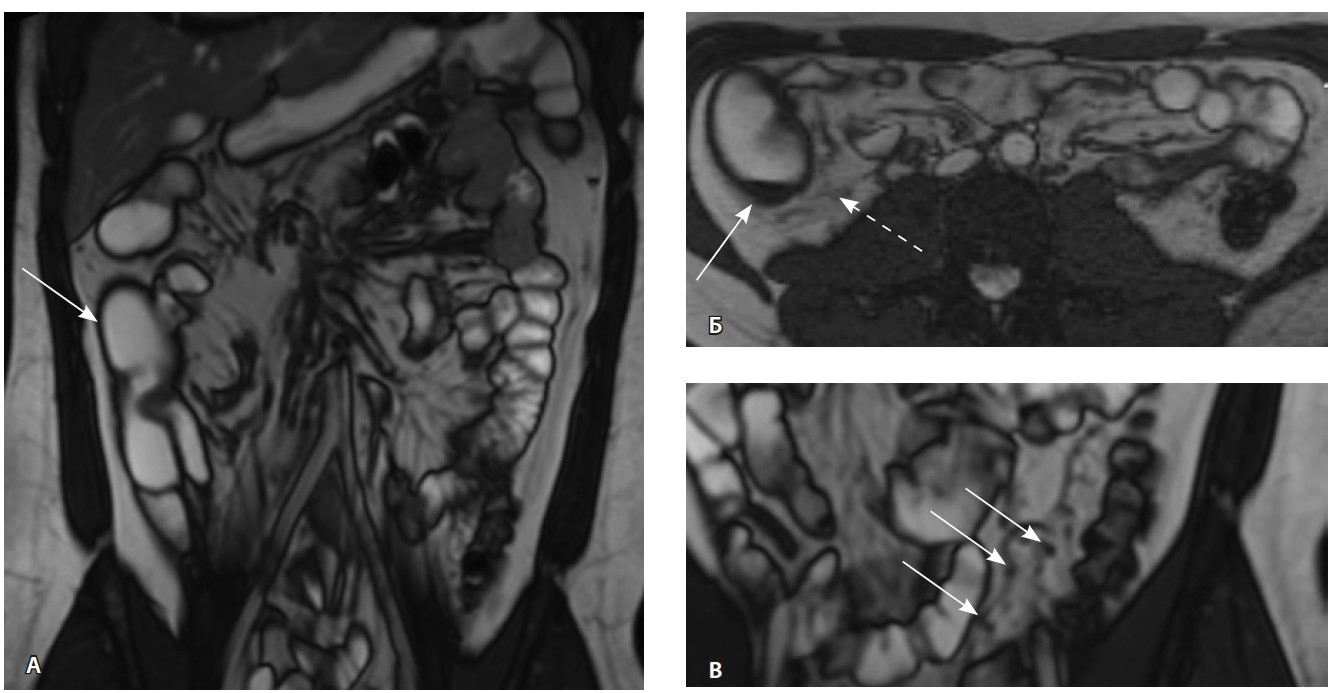

При мультиспиральной компьютерной томографии органов брюшной полости визуализировалась картина диффузного утолщения стенки толстой кишки с умеренным утолщением брыжейки и минимально выраженными явлениями лимфаденопатии в брыжейке (рис. 1).

Рис. 1. Мультиспиральная компьютерная томография органов брюшной полости с внутривенным введением контрастного вещества (йомепрол 350–100 мл), артериальная фаза: А – фронтальная проекция, Б – аксиальная проекция. Стрелками указано диффузное утолщение стенки толстой кишки и брыжейки